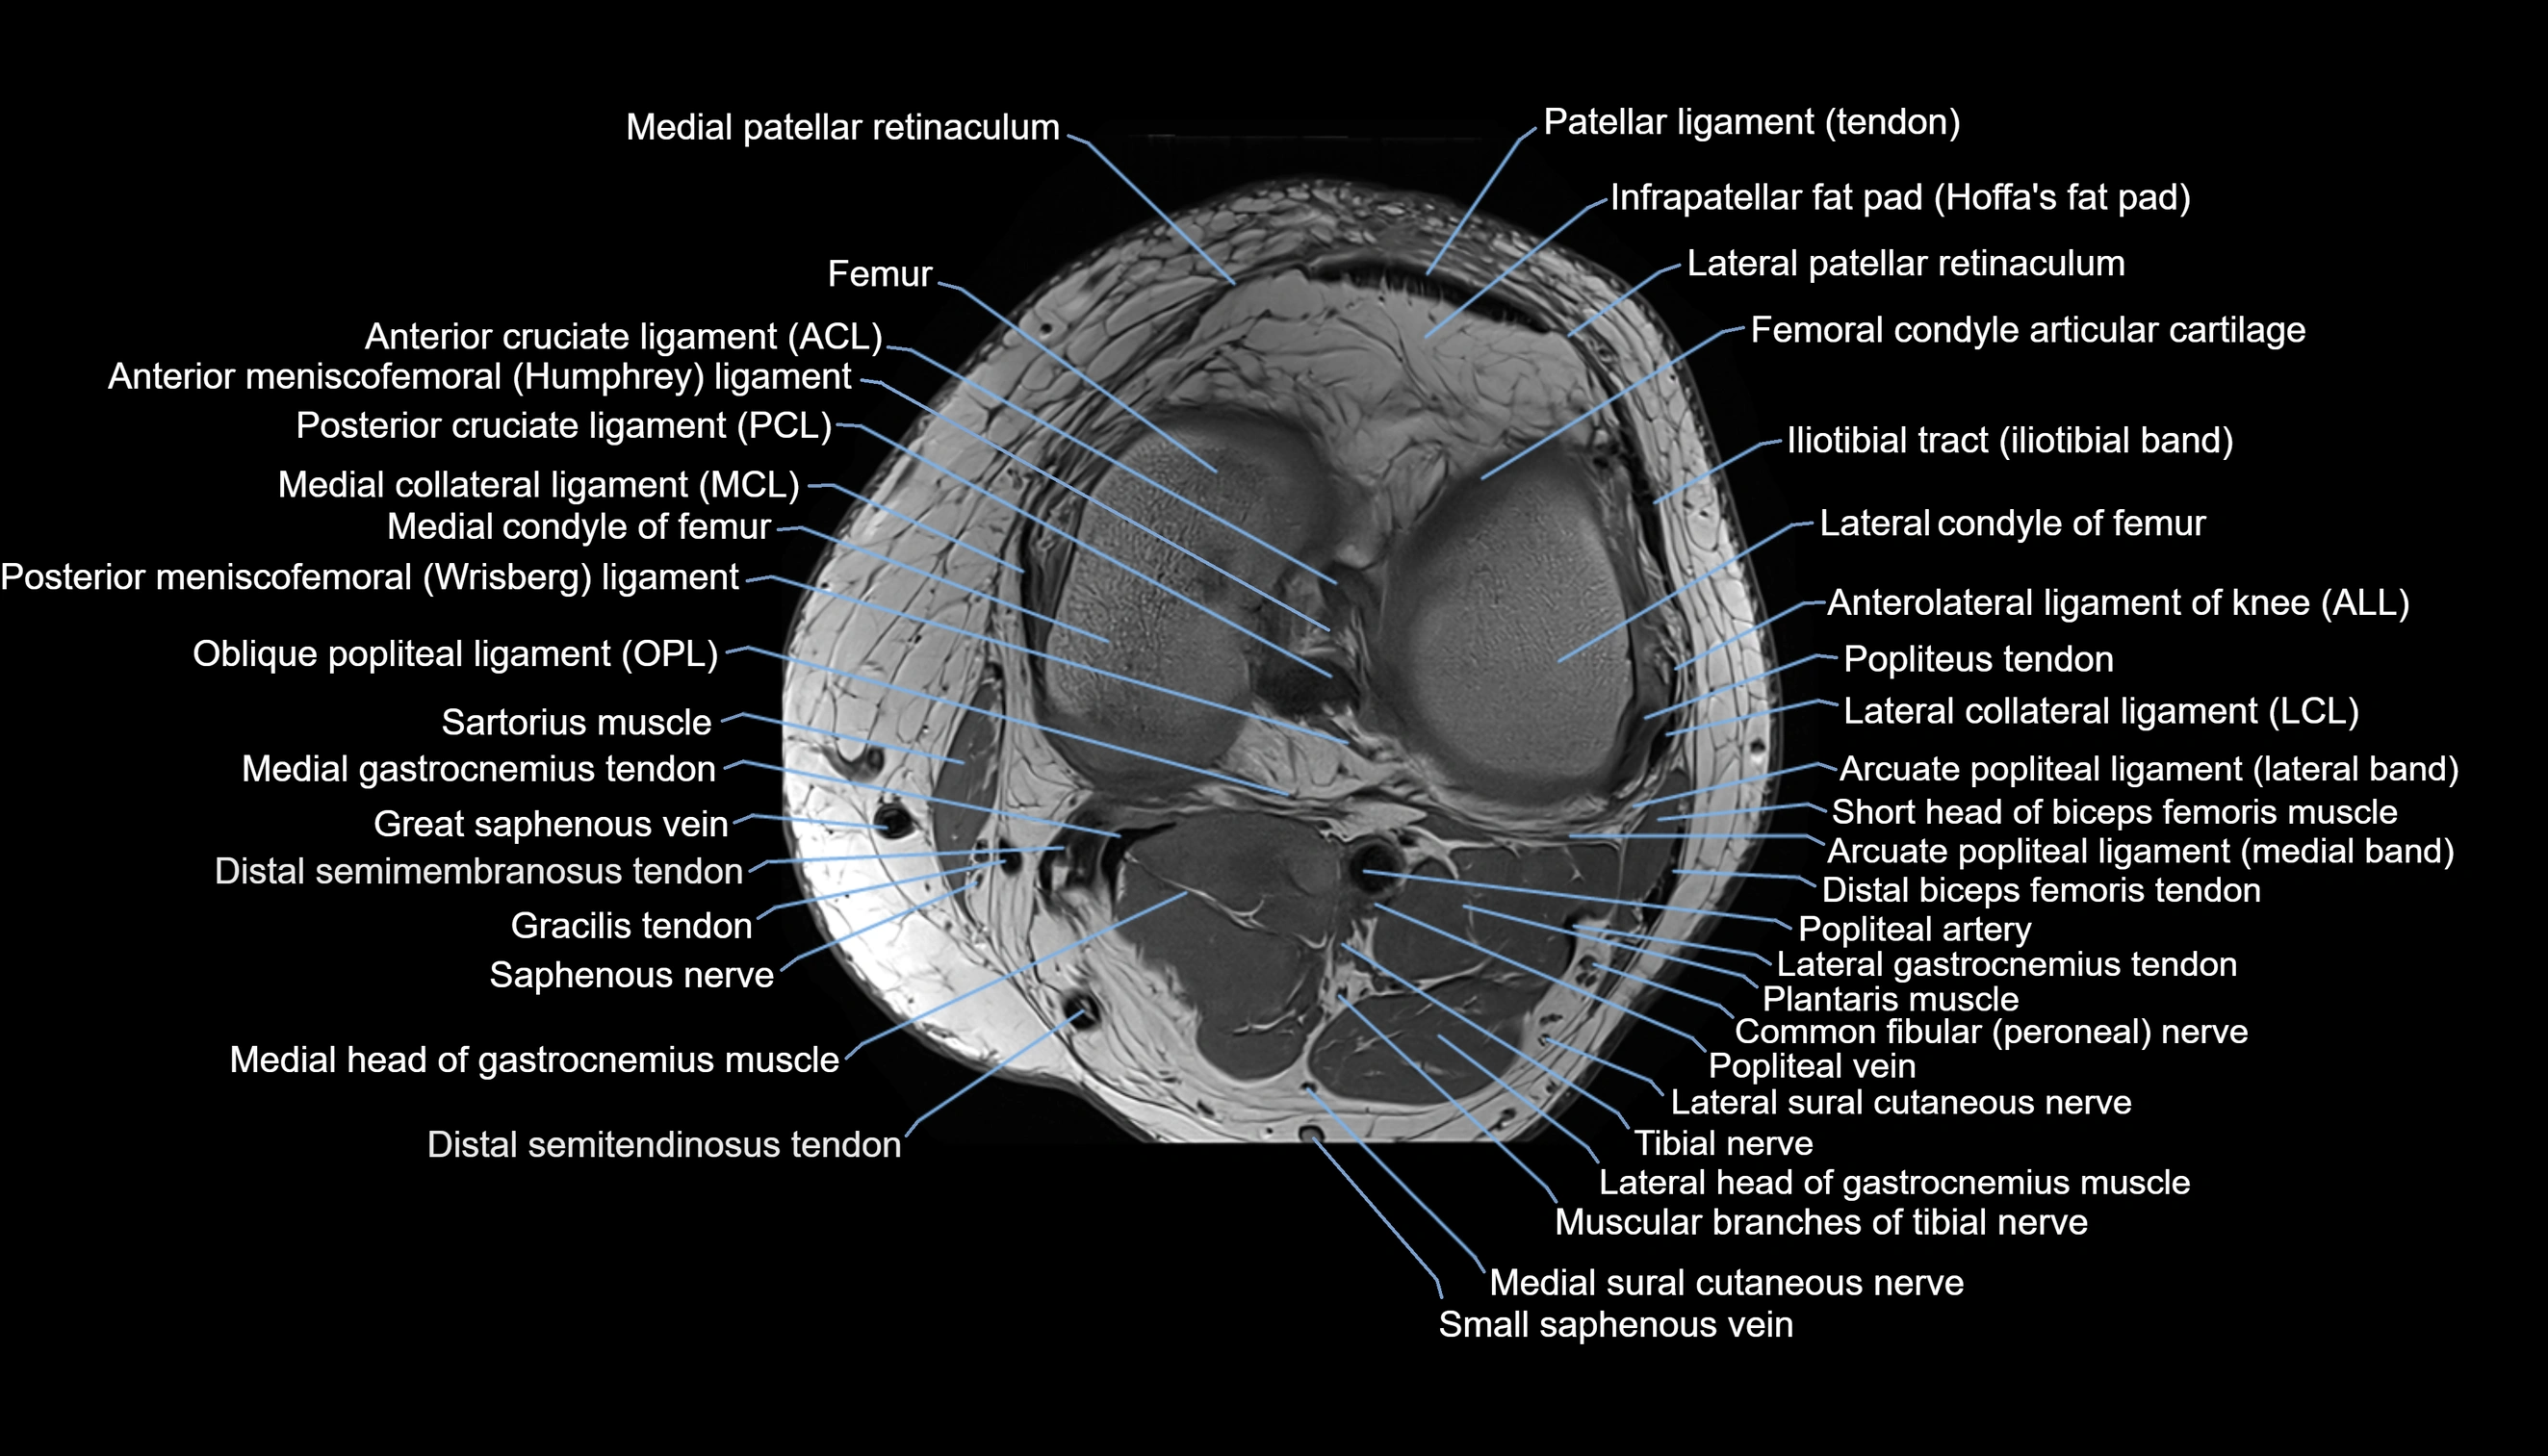

- Knee Joint